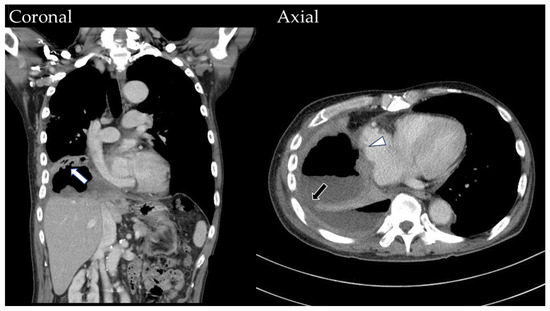

2. Case History